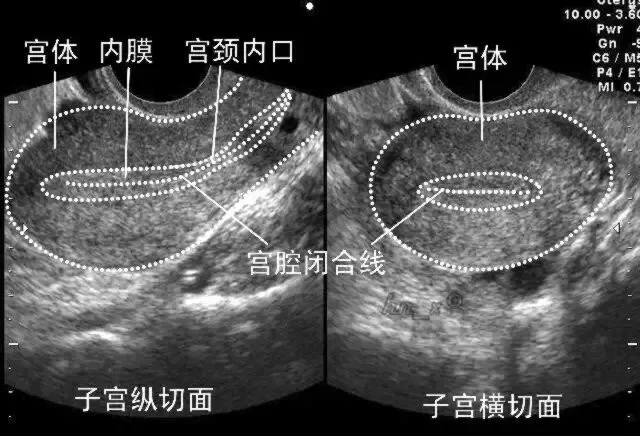

子宫位于骨盆中央,呈倒置的梨形,分为宫底、宫体、和宫颈。

●子宫内膜的测量

★测量标准切面:子宫体的正中矢状切面

★测量方法:垂直于子宫内膜中线,测量双层内膜外侧缘之间的最大厚度

★若存在宫腔积液时应分别测量两个单侧内膜厚度并相加

★若存在宫腔病变时应测量包含病变在内的内膜总厚度(黏膜下肌瘤不包括)